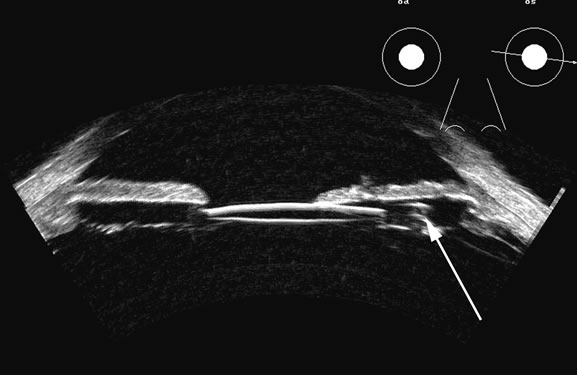

surface.8 A retracted “hyaloid” or posterior limiting membrane (PLM) of

the vitreous can be shown with most B-scan instruments, but

paradoxically a retracted vitreous may not be seen as well

with higher-resolution, more highly focused transducers because

they display less area of the reflective surface. Blood collected on

the surface of the PLM enhances this surface and may, in some cases, make

the PLM resemble a detached retina, since its anatomic dimensions

can be similar to the retina. Three differences may help distinguish the

two structures. First, kinetic scanning reveals a lack of attachment

at the optic nerve for a PLM. Second, the PLM is irregular in reflection

and thickness (usually thicker than the retina) between

the ora and the disc, and usually the surface cannot be traced forward

to the ora on the B-scan display. Third, the amplitude of the

echoes from the PLM is lower than from the retina, except when directly

perpendicular to the beam, where they may be similar in amplitude. Many

of these features of a PLM are demonstrated in Figure 7, whereas Figure 8 shows a typical detached retina. Hemorrhage shows good echogenic properties and presents a typical highly reflective vitreous body (Figs. 9 and 10). Asteroid hyalosis may resemble a vitreous hemorrhage except that the individual calcium deposits are even more reflective than hemorrhage and usually there is a clear anechoic zone between the retina and the retracted primary vitreous (Fig. 11). Synchysis scintillans is another condition with highly reflective regions in the vitreous due to cholesterol crystals. It is identifiable by the kinetic scan pattern of floating “snowflakes” that settle when the eye stops moving, just like the snowflakes in a child's snow globe. Since the “normal” vitreous is usually dissolved in this condition, the echoes come to rest on the retinal surface when the eye stops moving. An area or region of attachment of presumed vitreous to the ocular wall can be seen with kinetic scans and may indicate an area of stress or possible retinal tear. In diabetic retinopathy with proliferative membranes, the vitreous is often attached to a membrane, producing a typical cross-shaped elevation on a scan through the long axis of the proliferans. Right-angle or three-dimensional scans show the folded nature of the retinitis proliferans membrane (see Fig. 13). |